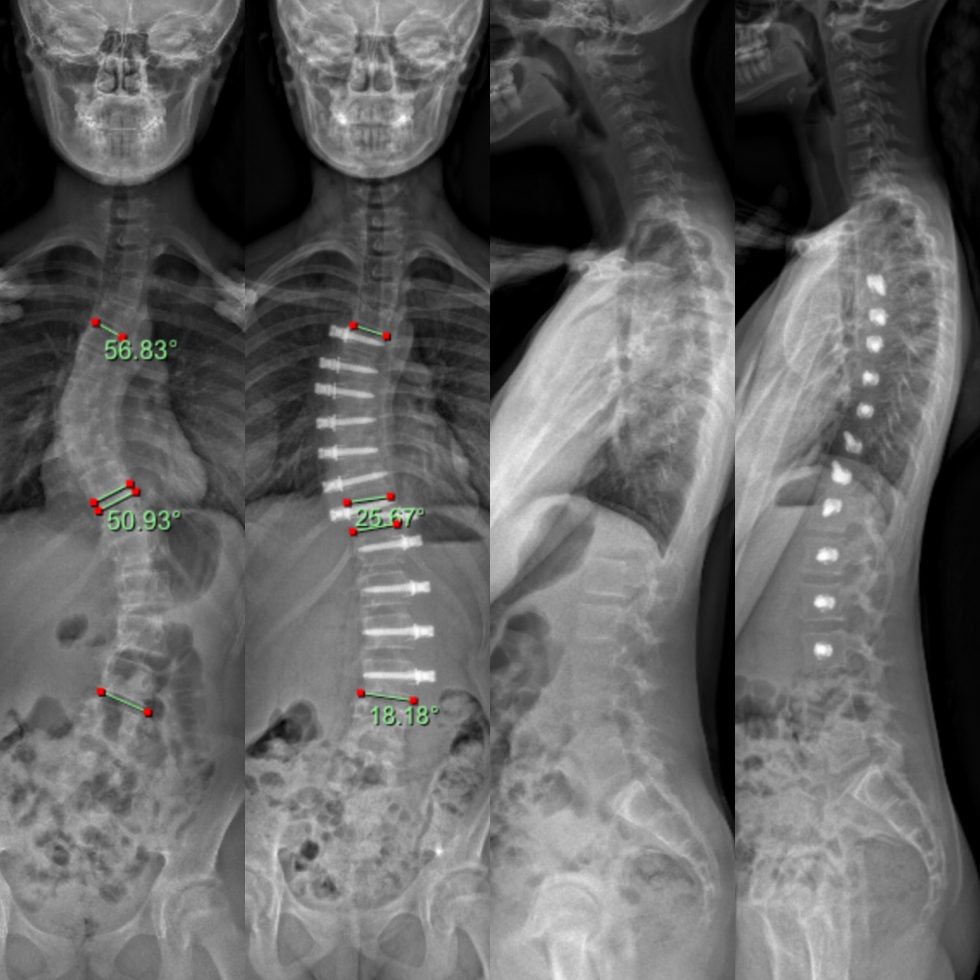

From scoliosiscenterofutah.com

Reduction of a severe scoliosis using scoliosis specific rehabilitation How Can You Prevent Scoliosis From Progressing Don’t overlook some of the common early signs of scoliosis, and always check. The best way to prevent scoliosis from getting worse is through proactive treatment applied as close to. Exercise is the recommended treatment for people with mild. Doctors cannot prevent scoliosis completely, but they can. Scoliosis can progress very quickly in teenagers, so the sooner you seek medical. How Can You Prevent Scoliosis From Progressing.